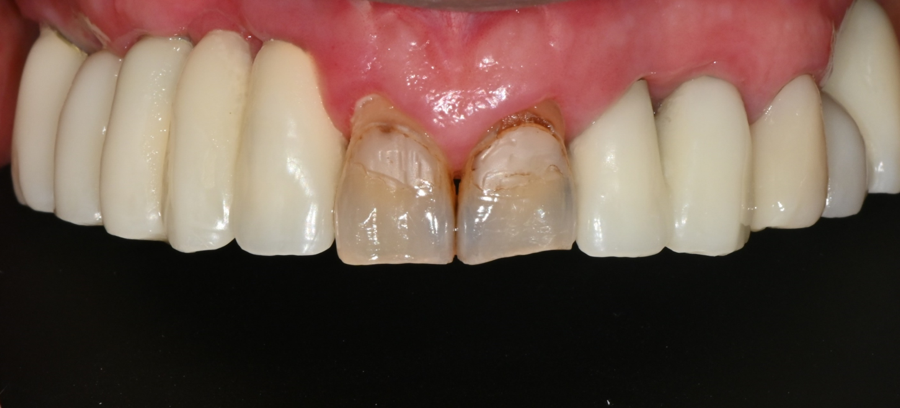

Condition at the time of the visit

The patient had old front tooth prosthetics

that had been used for a long time,

which had become yellowish,

the spaces between the teeth looked widened,

and they complained that they did not like

the shape of the front teeth when smiling.

The tooth surfaces were also significantly worn down,

and they said it was hard to smile in photos.